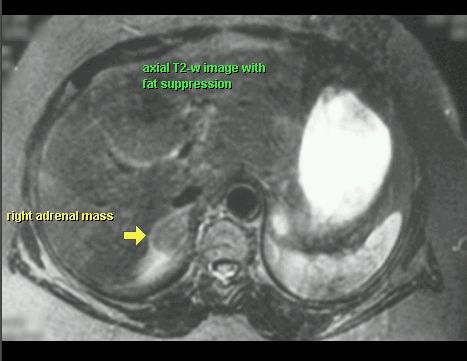

GRUCZOLAK NADNERCZA

MR